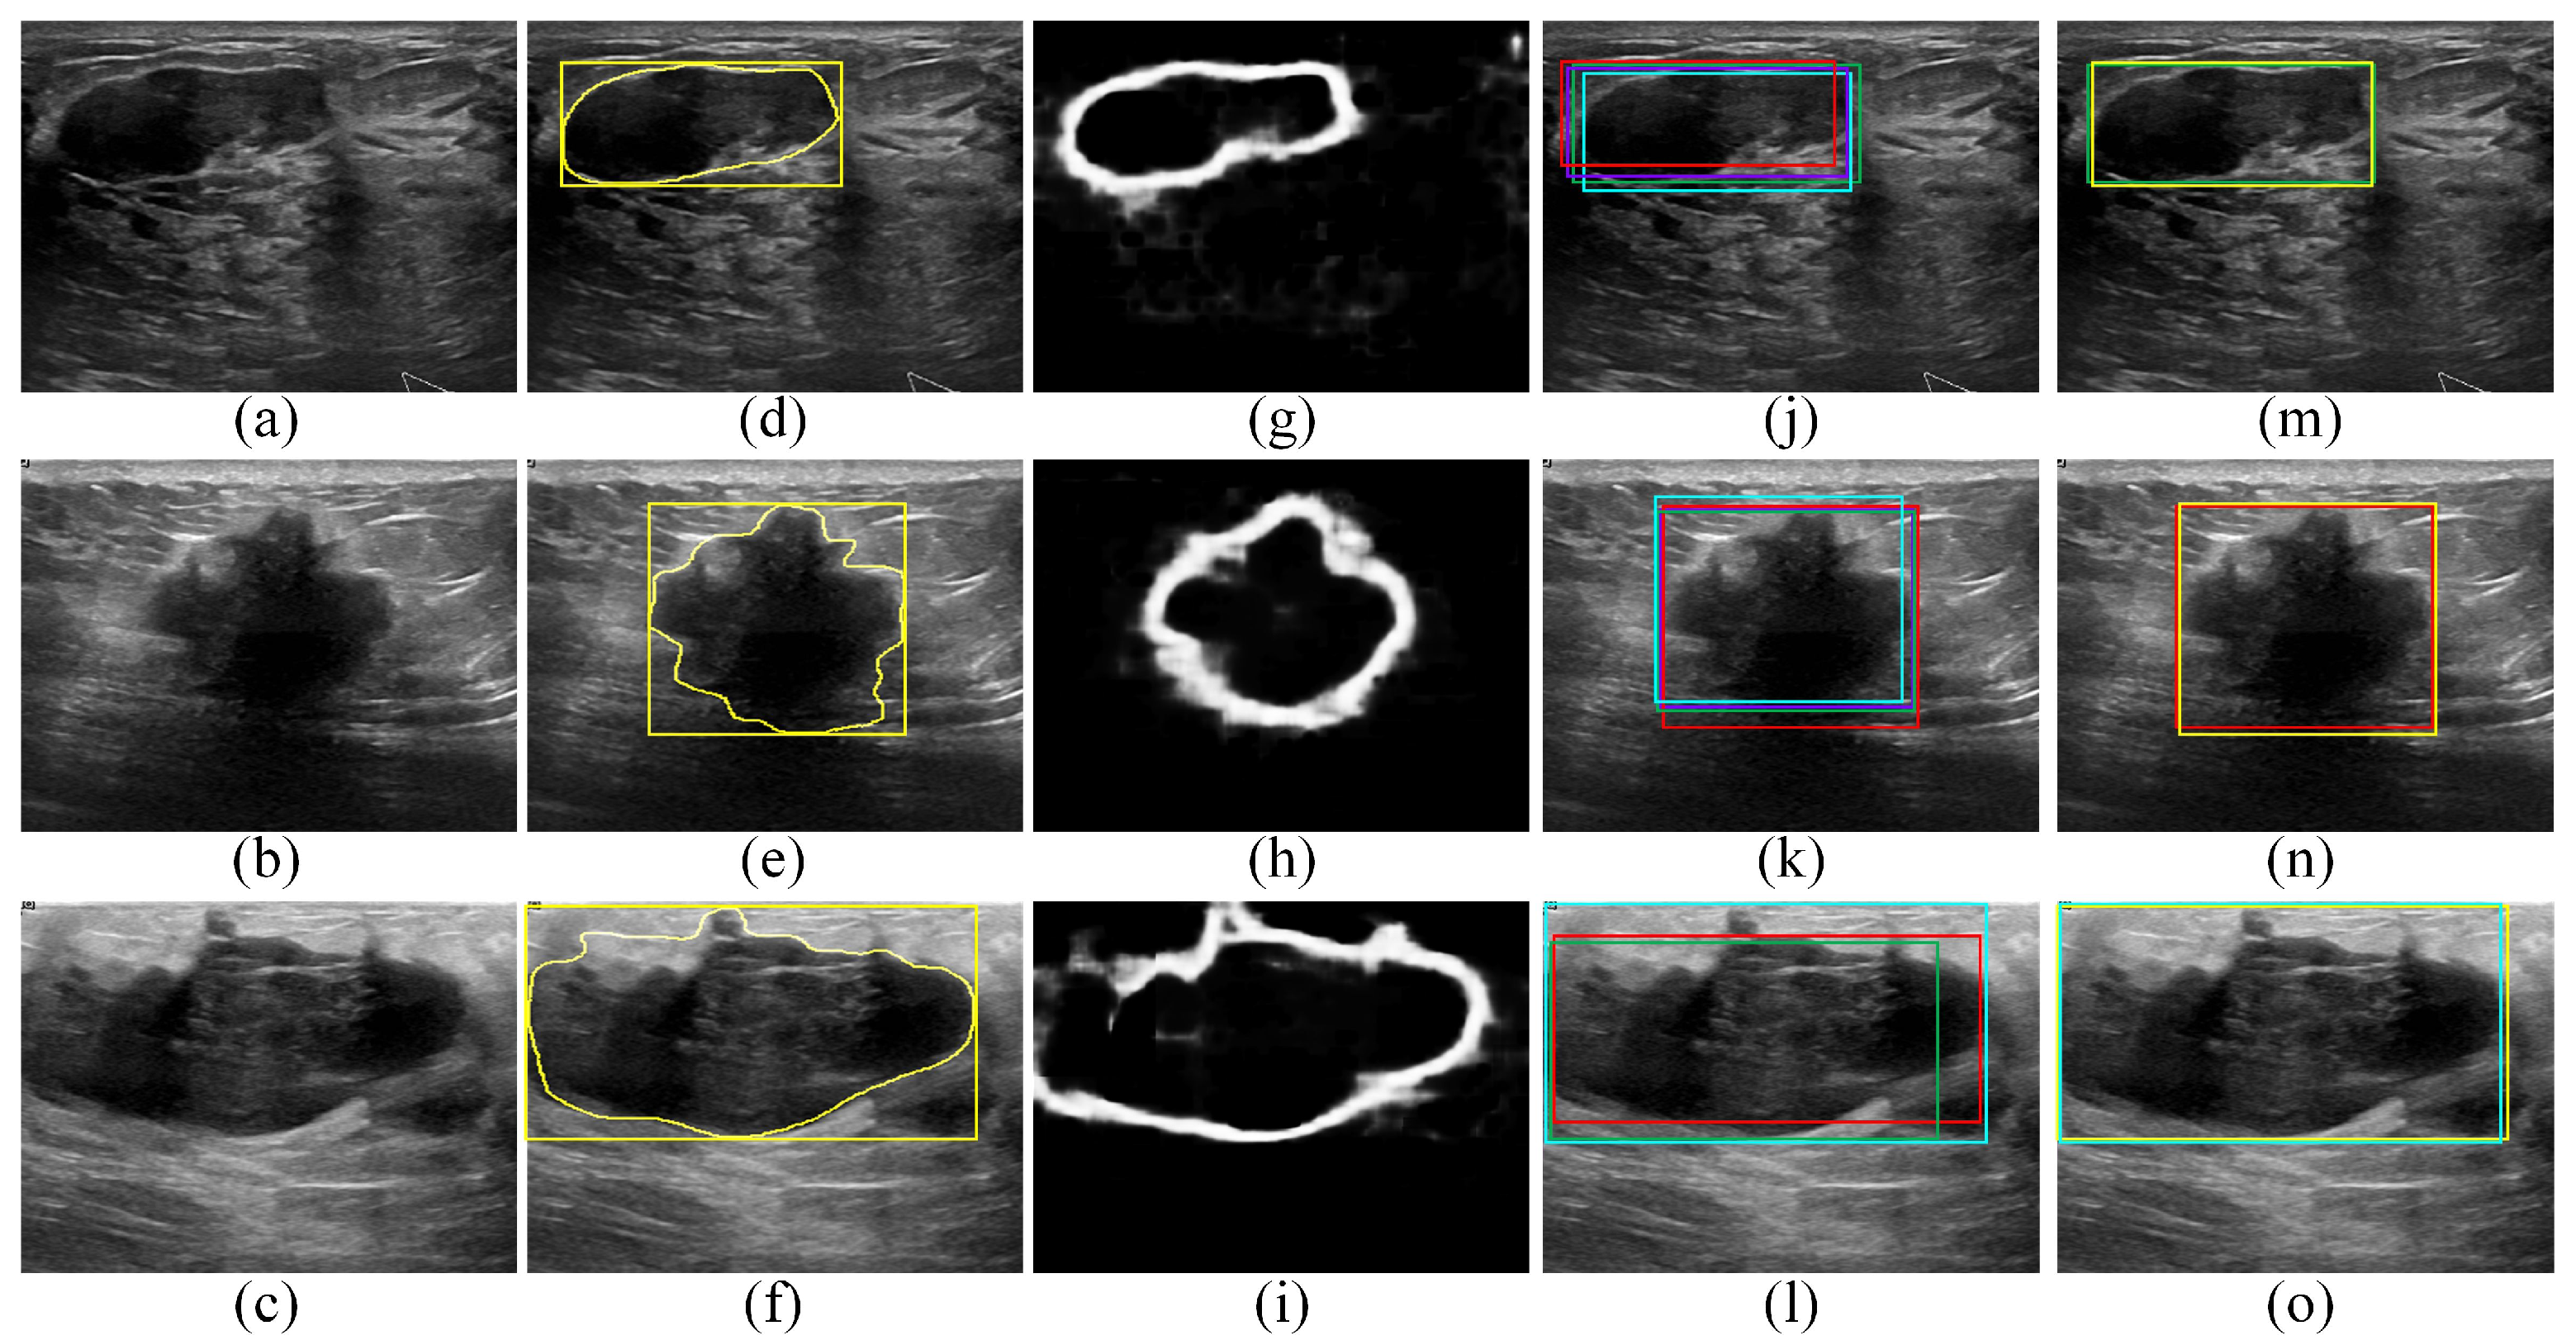

Figure 6 presents qualitative ROI localization results obtained for the BUSI dataset using the four deep learning object-detection models as well as the proposed edge-based selection method. The qualitative results provided in Figure 6 demonstrate the capability of the proposed edge-based selection method to process the ROI localizations generated by the four deep learning object-detection models and select an ROI that improves the localization of the region that includes the tumor.

Figure 6.

Qualitative results obtained for the BUSI dataset. (a–c) BUS images acquired for (a) benign tumor and (b,c) malignant tumors. (d–f) The gold standard tumor outlines (yellow outlines) and the gold standard ROIs (yellow boxes) overlaid on the BUS images. (g–i) The edge maps computed using the DexiNed model. (j–l) The ROI localizations generated by the Faster R-CNN (violet boxes), SSD (red boxes), EfficientDet-D0 (cyan boxes), and CenterNet (green boxes) models overlaid on the BUS images. In (l), the Faster R-CNN model failed to generate an ROI. (m–o) The ROIs selected by the proposed edge-based selection method as well as the gold standard ROIs (yellow boxes) overlaid on the BUS images. In (m–o) the proposed edge-based selection method selected the ROIs generated by the CenterNet, SSD, and EfficientDet-D0 models, respectively.